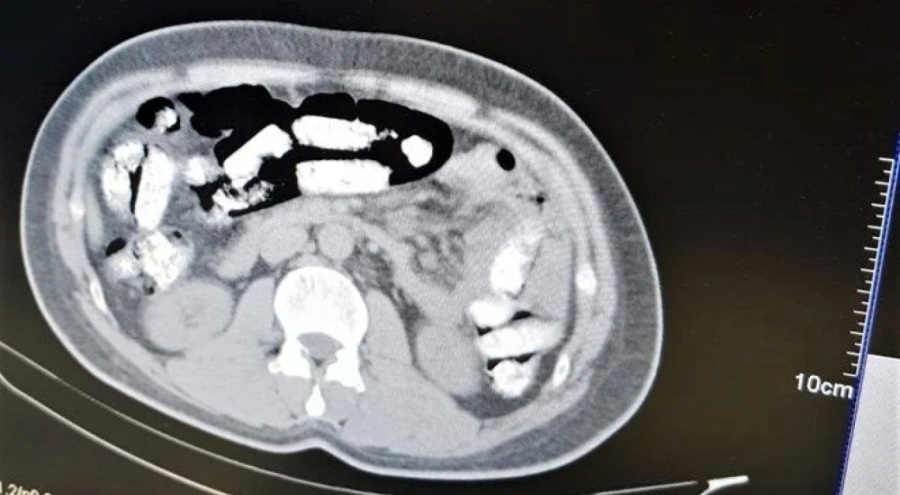

İran otobüsünde yolculuk yapan Abdulmennan S. isimli İran uyruklu kişinin yutma yöntemiyle uyuşturucu taşıdığı değerlendirilmesi üzerine, Erzincan Mengücek Gazi Eğitim ve Araştırma Hastanesinde zanlının bedeninden 106 fişek halinde toplamda 1 kilo 198 gram Afyon Sakızı bulundu.